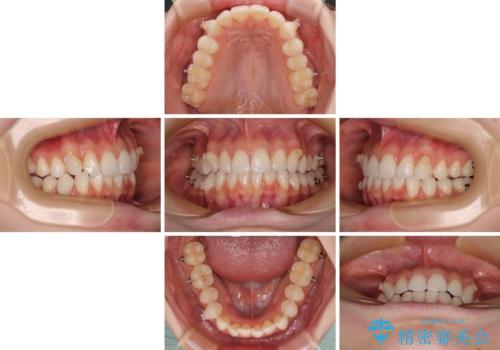

インビザラインによる上下歯列の拡大と、IPR(歯と歯の間を削る)にるスペースの獲得により、口元のデコボコとディープバイトを改善することとしました。

インビザラインは、装着していない時間がどれだけ短いかが、治療期間を大きく左右します。こちらの患者様は1日22時間以上、毎日欠かさず装着してくださったため、1年弱という短期間で満足のいく歯列に整えることができました。